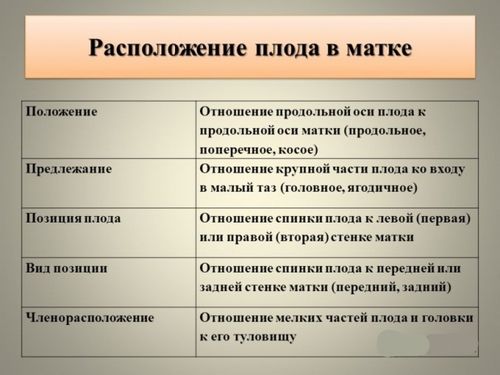

Положення і передлежання плоду при вагітності

Що таке положення плоду

положення плода - Це відношення його поздовжньої осі, яка проходить через його потилицю і таз до поздовжньої осі матки.

Розрізняють декілька типів положень плода:

■ Поздовжнє - Довгі осі матки і плода збігаються,

■ Поперечний - Поздовжні осі дитини і матки перпендикулярні один одному,

■ Косе - Поздовжні осі малюка і матки утворюють гострий кут, тобто це положення є середнім між першими двома.

Що таке передлежання плода

Передлежання плоду визначається частиною тіла, якої він спрямований до входу в родові шляхи. У медицині її називають предлежащей частиною. Передлежання плоду може бути головним - коли малюк розташований головкою вниз, тазові - коли біля входу в шийку матки лежать сідниці дитини, або поперечним - коли малюк лежить поперек до входу в родові шляхи і передлежачої частина тіла не визначається.